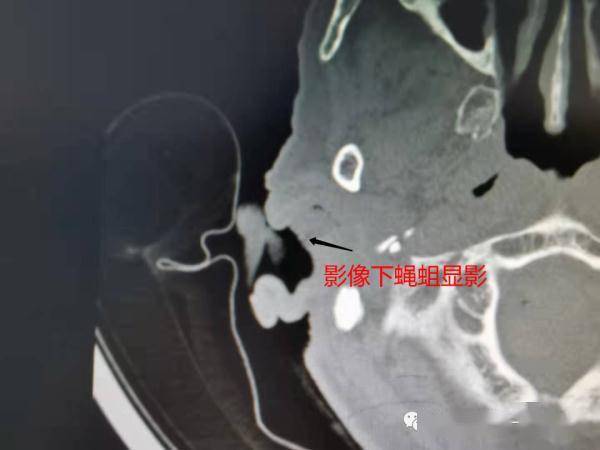

【虫体|头皮发麻!80岁老人总是耳朵疼,医生一看:20条活蝇蛆】于是医生立刻在视屏耳内镜下

进行专业处理 ,

共取出约20余条活体蝇蛆!